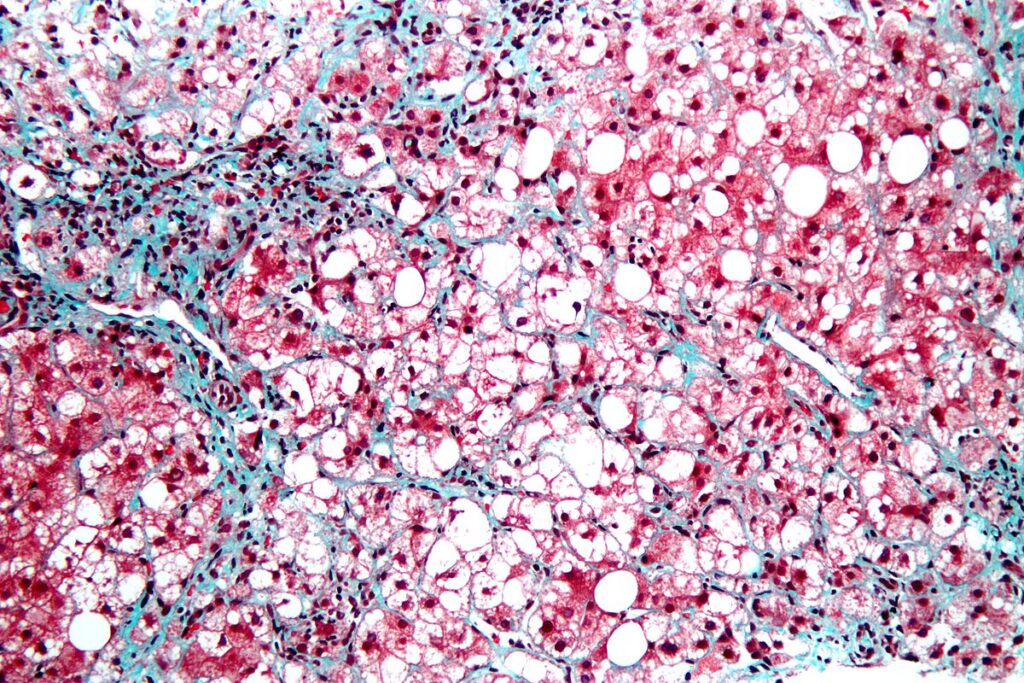

GLP-1–Receptor Agonist for Metabolic Dysfunction–Associated Steatohepatitis

In a randomized trial, semaglutide had favorable effects on steatohepatitis and fibrosis in liver biopsies.